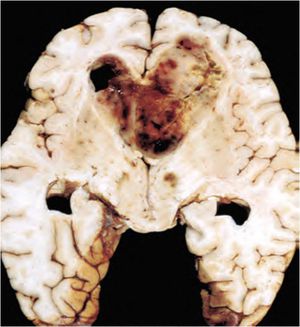

Grade 4 tumour of the glial cells is called as glioblastoma previously called as glioblastoma multiforme. The most common suite of Glioblastoma is Frontal lobe They are highly vascular and spread to the adjacent lobe and are called as Butterfly tumours